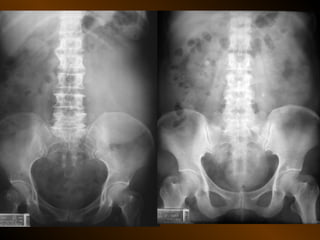

• Căng giãn đại tràng

TRIỆU CHỨNG HỌC KẾTQUẢ BÌNH THƯỜNG CĂNG VÀ Ứ KHÍ BỆNH LÝ TRONG ỐNG TIÊU HÓA: dạ dày, tá tràng, ruột non, đại tràng DÀY THÀNH ỐNG TIÊU HÓA BỆNH LÝ TỤ DỊCH TRONG PHÚC MẠC TỤ DỊCH NGOÀI PHÚC MẠC KHÍ TỰ DO TRONG KHOANG PHÚC MẠC TỤ KHÍ NGOÀI PHÚC MẠC TỤ KHÍ TRONG LÒNG, TRONG THÀNH TẠNG RỖNG VÀ TRONG CÁC CẤU TRÚC DẠNG ỐNG